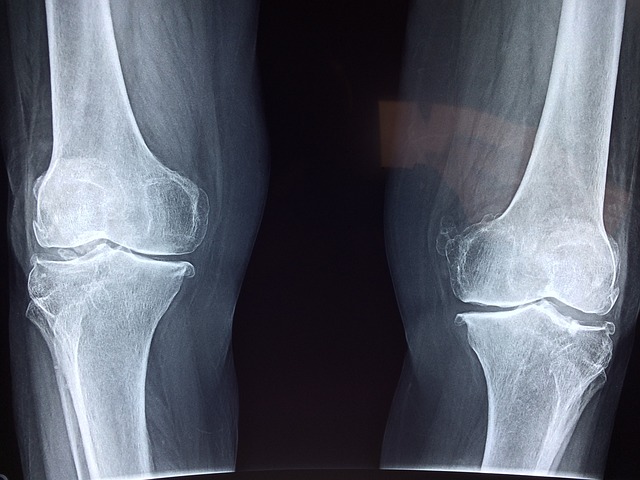

2) 관절 및 뼈 건강

콜라겐은 관절 연골의 주요 성분으로, 관절 통증을 완화하고 연골 손상을 예방하는 데 도움이 됩니다. 또한 뼈의 밀도를 유지하는 데 중요한 역할을 하여 골다공증 예방에 기여합니다.